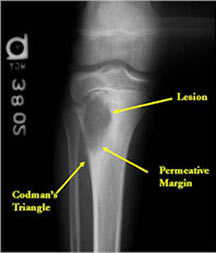

X-ray:

- Permeative lesion with indistinct border that is poorly marginated

- Osteolytic and expansile on X-ray with very little osteoid production

- May have Codman’s triangle and malignant appearing periosteal reaction in most cases

- Cortical destruction and soft tissue extension are common